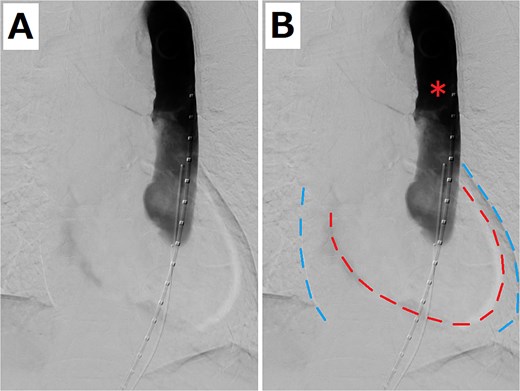

An 80-year-old woman presented with a progressively enlarging intrarenal AAA, measuring up to 50 mm. The patient’s performance status was relatively low; therefore, EVAR was selected to treat the AAA instead of open surgery. EVAR was performed under local anesthesia, and the procedure was conducted as usual (Gore Excluder 23 mm × 14.5 mm × 12 cm; W. L. Gore & Associates, Inc.; Delaware, USA). Ballooning was performed after implanting the main body stent graft and iliac limb extension stent graft. Subsequently, aortography was performed, which showed a type 1a endoleak. Therefore, ballooning was added at the top of the main body stent graft; however, the endoleak persisted. Thus, an additional stent graft (Gore Excluder 23 mm × 4.5 cm) was implanted at the upper end of the main body stent graft. Aortography was performed after ballooning; however, the flow was stagnating in the stent graft. At the same time, the pulse rate of the patient decreased suddenly, and she lost consciousness. She had pulseless electrical activity. Cardiopulmonary resuscitation was initiated, and an aortography was performed again. The presence of an aortic dissection was unclear; however, massive pericardial effusion was confirmed (Fig. 1). Cardiac tamponade by RTAD was suspected, and median sternotomy was performed emergently. After pericardiotomy, the pericardial cavity was filled with blood and hematoma, and spontaneous pulse returned after their removal. However, the adventitia of the aortic root was ruptured, and bleeding persisted. Therefore, ascending aortic replacement or aortic root replacement was performed. Cardiopulmonary bypass was established via left femoral artery perfusion and bicaval drainage. After the nasopharyngeal temperature reached 22°C, circulatory arrest was initiated. The ascending aorta was incised, and the lumen was checked. No tear was found at the intima of the ascending aorta and aortic root. Therefore, ascending aortic replacement was performed (Triplex Advanced 26 mm, Vascutek Terumo, Tokyo, Japan) with retrograde cerebral perfusion. The operation was completed without incident. The patient was extubated on the first postoperative day, and the postoperative course was uneventful. The postoperative enhanced computed tomography (CT) revealed that the entry of the dissection existed at the top of the stent at the abdominal aorta, and the dissection was connected to the distal side of the ascending aortic artificial graft (Fig. 2). The patient was discharged 30 days postoperatively. At the 1-year follow-up, the aorta treated for dissection remained stable.

(A) Aortography when the patient had pulseless electrical activity. (B) Pericardial effusion is shown. The red and blue dashed lines indicate the edge of the heart and pericardium, respectively. The red asterisk shows that the flow was stagnating in the stent graft.